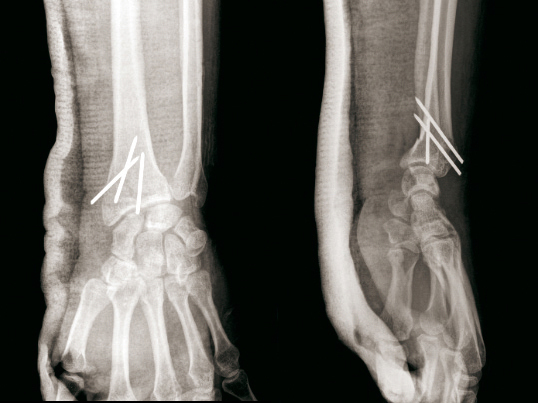

© Henry Coudane, Frédéric Éloy (La Revue du Praticien) Embrochage intrafocal selon Kapandji avec trois broches. (À gauche) Radio de face. (À droite) Radio de profil.